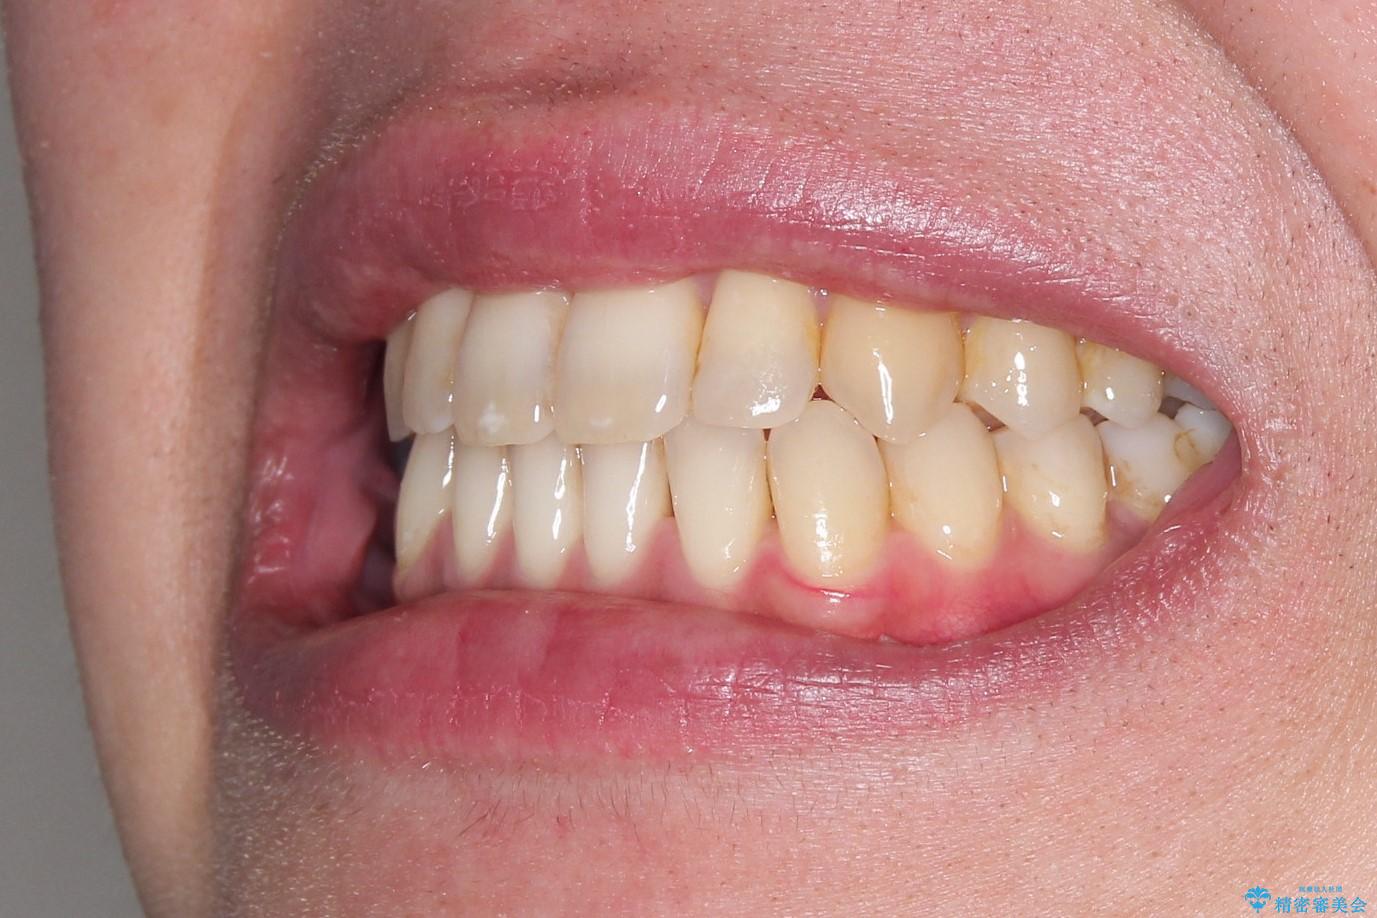

Invisalign インビザライン によるガタつき、受け口傾向の改善

奥歯の位置関係の修正は難儀することが多いマウスピース矯正ですが、割とスムーズに奥歯の位置関係の修正をすることができました。

クロスバイトもきれいになり、きれいな歯並びとなりました。